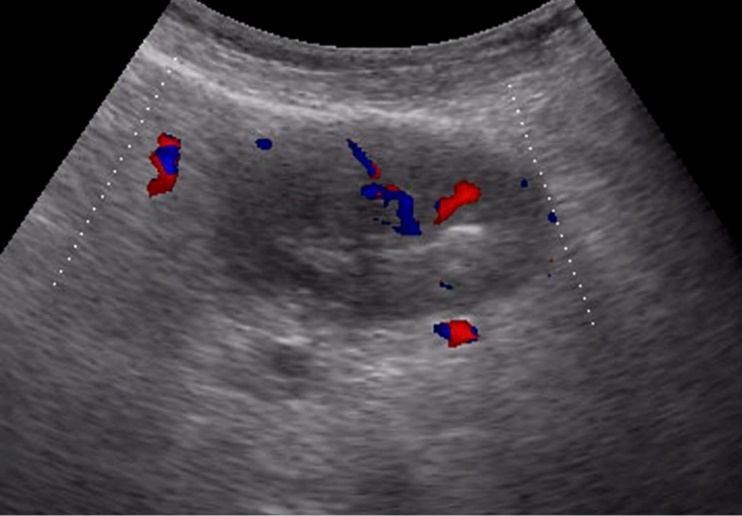

Metastasis to the regional lymph nodes was diagnosed in 52 cases. Ultrasonographically, this was detected in 37 (71.2%) cases. Sonographic features of lymph node metastatic lesions are: an increase in their thickness, a decrease in echogenicity, deterioration or lack of differentiation of the peripheral and central parts of the nodes, recording of color vascular signals inside the nodes (Figure 18, Figure 19).

Figure 18.Metastasis to the retroperitoneal lymph node in gastric cancer of the antrum of T3 stage. The longitudinal size of the lymph node is increased to 5 cm, the echo is significantly reduced, along the periphery of it is visible color vascular signals in tissue Doppler mode.

Figure 19.Metastatic affected lymph node in gastric cancer of the anterior wall of the stomach of stage T4. Significantly enlarged lymph node, echogenicity reduced, large vascular signals in color Doppler mode visible in the center.